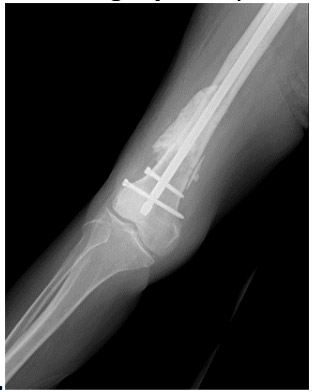

Post-surgery: The X-ray shows the application of bone cement and nails to the site of the removed metastatic focus.